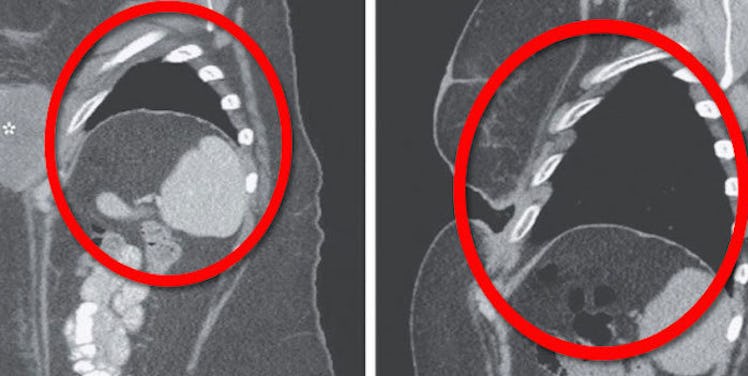

The woman's tumor completely disappeared, leaving behind a gap in her body.

The study notes,

She was left with a cavity... there was no evidence of tumor.